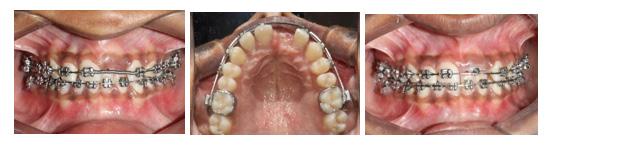

All selfies at T0 and T1 were cropped up to the clavicle of the subject if visible. The backgrounds of the selfies were removed and turned white with the help of Adobe Photoshop CC 2020 version 21.1 software package (Adobe Systems, San Jose, CA). One example of pre-treatment and post-treatment selfies of a subject in skeletal class I is illustrated in Figure 1A and 1B, in skeletal

Figure 1: Skeletal Class I Group (SCI) Male.

A-Pre-treatment (T0) Selfie; B- Post-treatment (T1) Selfie; C. Pretreatment Profile Silhouette (T0). D. Post-treatment Profile Silhouette

Figure 2: Skeletal Class II Group (SCII) Female.

A-Pre-treatment Selfie (T0), B- Post-treatment Selfie (T1). C. Pretreatment Profile Silhouette (T0), D. Post-treatment Profile Silhouette (T1).

Figure 3: Skeletal Class II Group (SCII) Female.

class II is illustrated in Figure 2A and 2B, and in skeletal class III is illustrated in Figures 3A and 3B.

All profile photographs at T0 and T1 were cropped up to the clavicle of the subject. Profile photographs were converted into black silhouettes against a white background using Adobe Photoshop CC 2020 version 21.1 software package (Adobe Systems, San Jose, CA) One example of pre-treatment and posttreatment profile silhouettes of a subject in skeletal class I is illustrated in Figure 1C and 1D, in skeletal class II is illustrated in Figure 2C and 2D, and in skeletal class III is illustrated in Figure 3C and 3D.